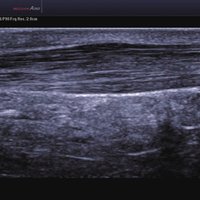

Das Samsung Accuvix A30 ist ein hochwertiges Ultraschallsystem, das mit seiner 3D-Technologie herausragende Ergebnisse ermöglicht. Das Sonographiegerät besitzt 5 Sondenanschlüsse und ist mit 20 unterschiedlichen Schallköpfen kompatibel. Mit dem A30 können Schallköpfe vom Typ Konvex, Mikrokonvex, 3D-Konvex, CW, Phased Array, Linear und Endokavitär verwendet werden. Bei zwei der Sonden handelt es sich um S-VUE Ultraschallsonden, die durch ihre höhere Bandbreite noch feinere Scans erzeugen.

Das Samsung Accuvix A30 ist mit 20 unterschiedlichen Schallköpfen kompatibel. Folgende Konvex-, Mikrokonvex-, 3D-Konvex-, CW-, Phased Array-, Linear- und Endokavitär-Schallköpfe werden unterstützt:

1 L4-7 Linear 4-7 MSK, Gefäße, Tiefe Venen

2 L5-13IS Linear 6-12 MSK, Weichteile, Gefäße, Brust

3 L5-13/50mm Linear 5-13 MSK, Weichteile, Gefäße

4 LS6-15 Linear 6-15 MSK, Weichteile, Gefäße

5 L7-16IS Linear 7-16 MSK, Weichteile, Gefäße, weibliche Brust, Pädiatrie, Oberfläche